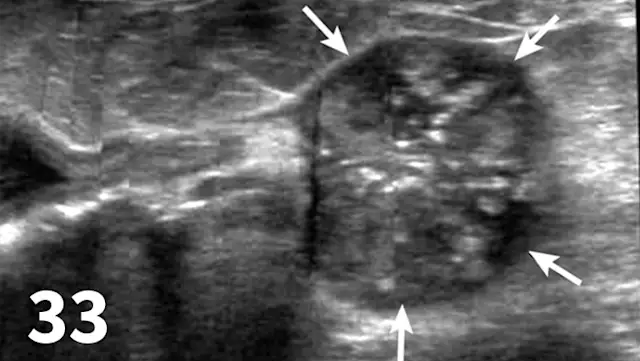

Survey radiography can be used to evaluate the size, shape, and opacity of the prostate gland (Figures 31 and 32). Ultrasonography has the advantage of providing tissue-architecture information. Prostatic abscesses, internal cysts, and paraprostatic cysts are readily visualized on ultrasonography. Ultrasonography can also aid in diagnosing benign hyperplasia (homogenous echotexture with intact capsule) and prostatic neoplasia (heterogenous with course echotexture and irregular margins) (Figure 33) and with identifying any potential source of excess androgen production (eg, adrenal glands, retained testes) in cases of suspected squamous metaplasia of the prostate gland. Mineralization of the prostate in a neutered dog is suggestive of neoplasia and can be detected by both survey radiography and ultrasonography. Sublumbar lymph nodes can also be evaluated by ultrasonography, whereas radiography is best for evaluating the adjacent lumbar spine (Figures 34 and 35).

Figure 31.

The prostate gland (arrows) in this intact male dog is enlarged but normal in shape with smooth margins and soft tissue opacity. Although this is consistent with benign prostatic hypertrophy, ultrasound would be useful to further define tissue architecture.